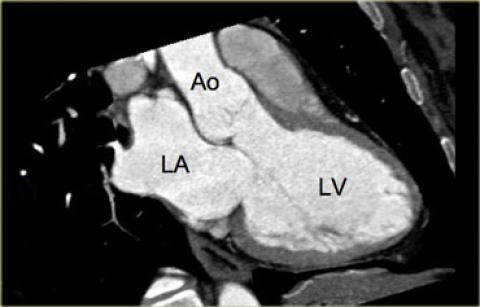

Vue 3 cavités (long axe apical)

- Marqueur sur le bord entre valve mitrale et aortique

- Rotations

- Vue de la chambre de chasse G, OG et VG